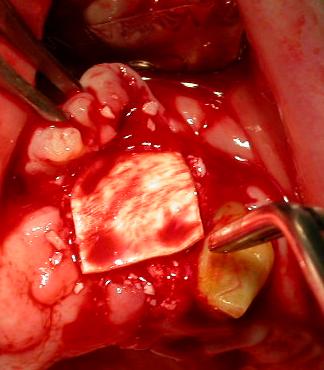

Sul terzo sito implantare, in zona 2.2, durante la perforazione si è avvertita una scarsa densità ossea, per cui si è sottodimensionato il sito limitandosi alle frese a spirale di ø 2,00- 2,5 mm. sottodimensionando e scegliendo l’utilizzo di un impianto da Ø 3,30 h.10,0 per ottenere una migliore stabilità primaria. Durante l’inserimento manuale dell’impianto e nelle dette fasi d’avvitamento, giunti al termine della lunghezza di lavoro desiderata, si è notata una fenestrazione della corticale vestibolare, per cui è stato utilizzato tessuto osseo eterologo (Bio-gen Mix, Bioteck) e una membrana di collagene (Biocollagen, BiotecK).

(Foto 21-22-23-24 fenestrazione impianto zona 2.2 – osso eteroogo e menbrana)

Bio-Gen Mix: è una miscela di granuli di spongiosa da 0,5 mm e di granuli di corticale da 1 mm, tali da garantire un’elevata osteogenesi grazie all’assenza del processo di calcinazione nel procedimento di lavorazione che avviene mediante processi fisico-chimici ad una temperatura massima di esercizio di 130° in ambiente umido. Il tessuto osseo finale costituito da matrice minerale ossea a struttura anatomica non modificata, viene proposto sia in granuli di tipo corticale o spongiosa, che in blocchi derivati da sezioni femorali, con tempi di riassorbimento e matabolizzazione da 4 a 6 mesi. Il materiale deve essere inserito in cavità ossee a strati e gli spazi tra i vari granuli saranno invasi da matrice ossea neoformata che andando incontro a mineralizzazione darà vita a tessuto osteoide precoce dotato di eccellenti caratteristiche meccaniche, che verrà poi metabolizzato in 4-6 mesi e sostituito da osso endogeno. Biocollagen “Bioteck”: è una membrana di collagene naturale equino, (tendine di achille) deantigenato, anallergico, liofilizzato, 100% riassorbibile, per rigenerazione ossea guidata, che assicura la protezione dell’invasione epiteliale per almeno 4-6 settimane. Il processo di deantigenazione enzimatica inibisce completamente la replicazione batterica sul tessuto osseo, privando i batteri del loro substrato nutritivo. Costituisce un valido ausilio nell’utilizzo di biomateriali, in forma granulare ove non sia possibile il contenimento dei lembi di chiusura della cavità, per mancanza o insufficienza degli stessi. Inserito in cavità ossee, viene reidratato per 5 minuti mediante fisiologica sterile che ne migliora le proprietà meccaniche, il tempo di rilascio varia da 2 a 5 giorni, il prodotto presenta un comportamento neutro in fase di metabolizzazione, subendo una totale degradazione in 4-6 settimane, con assenza di infiammazione locale; in caso di forte sanguinamento il prodotto agisce come emostatico.

Applicazione di tessuto osseo eterologo Bio-Gen Mix (BiotecK)

La tecnica chirurgica di incremento verticale di cresta si rende necessaria quando la quantità di osso disponibile in senso verticale non garantisce la stabilità a lungo termine degli impianti. Tale tecnica è considerata tra le più difficili tra le procedure che si basano sui principi della rigenerazione guidata dei tessuti ossei (GBR). L’obiettivo della GBR è rappresentato dalla formazione di nuovo osso innestato contemporaneamente al posizionamento di un impianto nella sede di un difetto osseo.

(Foto 25-26 Applicazione membrana di collagene Biocollagen (Bioteck) sutura in seta e controllo rx-rvg)